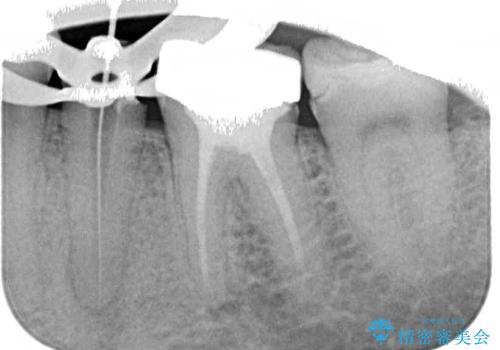

レントゲン写真より、既に根管治療がされている歯であり、根尖部に骨透過像が認められました。

特に症状はありませんでしたが、根管治療を希望されたため、まずは根管治療を行うこととしました。

根管治療の際に、咬み合う上顎の銀歯が内側に入り込んでいることも気になるとのことであったため、部分矯正を行い、その後上下を同時に補綴治療することとしました。